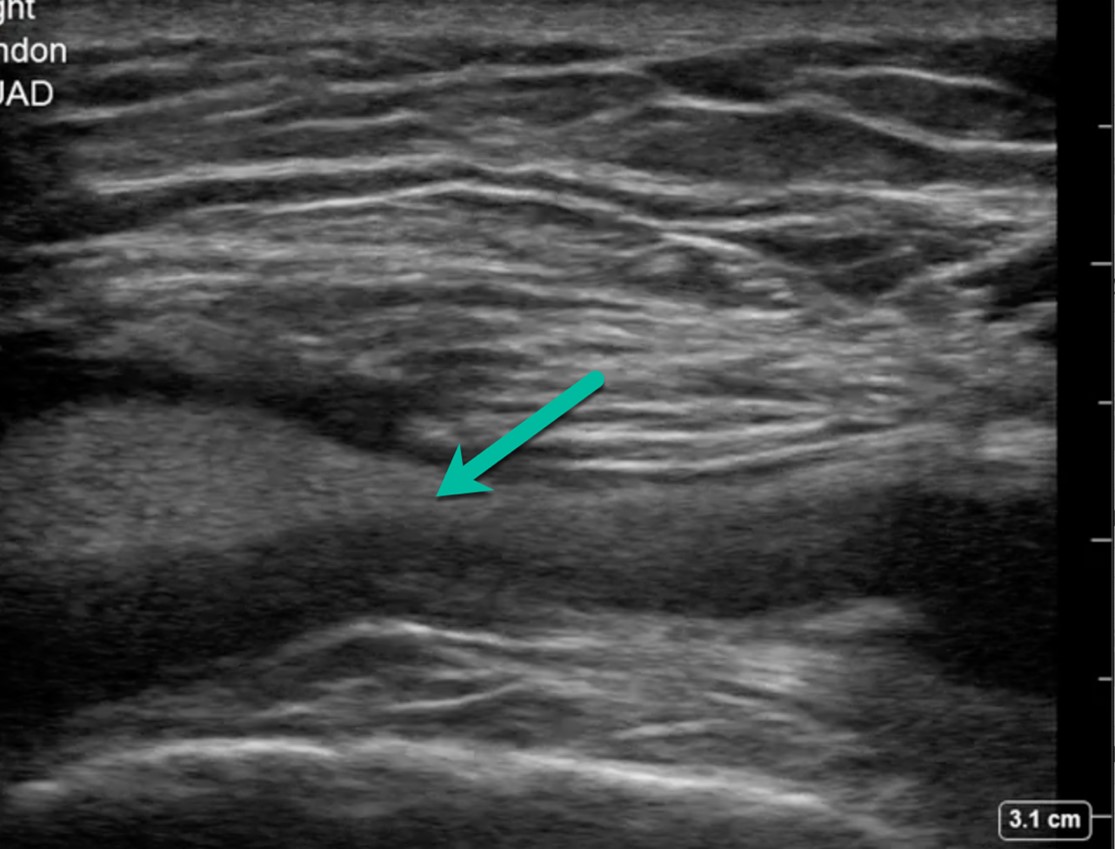

Using the high-frequency linear probe, typical views are obtained superior and inferior to the patella, as well as medial, lateral, and posterior to the knee joint. Views superior and inferior to patella assess for the integrity of the quadriceps and patellar tendons, the patella, as well as presence of knee effusion. Normal examination of the overlying skin and absence of cobblestoning of the soft tissue on ultrasound lessens the likelihood of cellulitis and abscess. Figure 1 shows the anterior ultrasound view of the knee, the patella. An intact patella should demonstrate the uninterrupted hyperechoic curvature of the cortical surface. In figure 1, we see an unmistakable cortical disruption (between the two red arrows), indicating a patellar fracture. Knee effusions will appear as an anechoic collection, indicated by the blue arrow, deep to the tendons. (Fig. 2) Medial and lateral views can also demonstrate effusions. Complex effusions such as hemarthrosis appear as hypoechoic collections if clotting has occurred. Figure 3 demonstrates a traumatic hemarthrosis identified by the green arrow. Figure 4 shows another simple knee effusion, indicated by the green arrow, without a history of trauma. Aspiration in the emergency department or office can be useful in directing therapy. In Figure 4, we see the needle approaching the effusion from the left side of the screen highlighted by the red arrow. Lastly, the posterior aspect of the knee contains the popliteal vessels. The popliteal vessels should be identified by Color Doppler, allowing differentiation from the non-vascular structures. Figure 5 shows a cystic non-compressible, anechoic structure without internal echoes within the popliteal fossa highlighted by the yellow arrow.

Figure 3